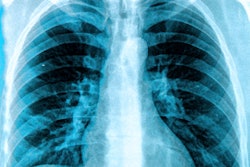

The SARS-CoV-2 virus can be transmitted from droplets when an infected person coughs, sneezes, or speaks. Viral transmission can occur through airborne droplets contaminated with the virus or when a person touches a contaminated surface. COVID-19 is the respiratory disease that can develop from infection with the SARS-CoV-2 virus.

National University Hospital has used its imaging equipment extensively. The facility has portable x-ray devices but not a portable CT scanner, so its staff has designated a stationary CT system specifically for COVID-19 patients or suspected cases to eliminate the potential for cross-virus contamination among imaging systems. The CT scanner also is located a short distance from the hospital's isolation ward.